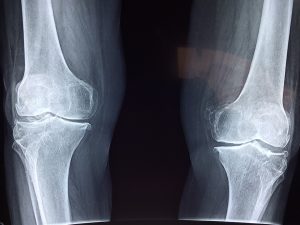

L’osteofitosi può colpire diverse articolazioni ma tra le sedi più comunemente interessate da questa condizione troviamo il ginocchio, l’anca, il piede, la mano, il collo (osteofitosi cervicale) e la fascia lombare. Naturalmente, a seconda delle collocazione del problema potrebbero presentarsi dei sintomi differenti ma in tutti i casi localizzati in quell’area.